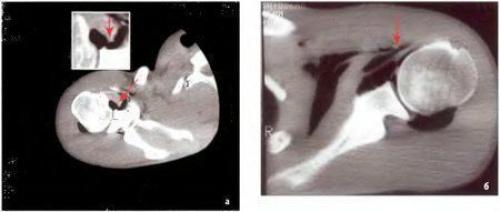

Рентгеноморфологическое изображение травматической нестабильности плечевого сустава на компьютерных томограммах (КТ) выглядит как отделение суставной губы с капсулой плечевого сустава от суставного отростка лопатки с заполнением этого дефекта рентгеноконтрастным кислородом.

На КТ в аксиальной проекции признаки повреждения Банкарта — отрыв суставной губы от переднего края суставного отростка лопатки (1)

Повреждение Хилла-Сакса в виде импрессионного перелома задненаружного отдела головки плечевой кости

Таким образом, при компьютерной артропневмотомографии у всех пациентов с острой передней посттравматической нестабильностью плечевого сустава выявляют рентгенологические признаки классического повреждения Банкарта — отрыв суставной губы с капсулой плечевого сустава от передненижнего края суставного отростка лопатки и повреждения Хилла-Сакса — хондральный или компрессионный перелом головки плечевой кости.